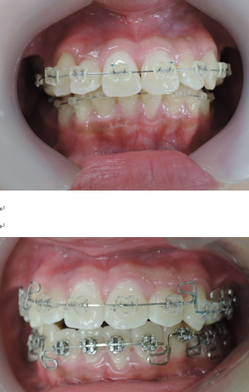

出来るだけ見えにくい矯正装置(ブラケット)を上下顎に装着して歯並びを整えていきます。矯正装置を装着後3日から7日ぐらいまでの間は歯が動きだすために軽い痛みを感じることがあります。

また、矯正装置が口腔内という敏感なところに装着される事で異物感を感じます。そのために本能的に装置を取ってしまいたいと考えて、当日から翌日位は矯正装置が脱落する事が多いです。

次にMEAW(マルチループ)を利用する事で咬み合わせの高さや前歯の傾斜を整えていきます。

また、MEAW(マルチループ)はゴムを24時間使用する事で最大の効果を発揮することが出来ます。

当院では簡易なMEAW(マルチループ)を使用する事で上下の前歯部をより綺麗な歯並びにしていきます。

この時にも24時間使用するゴムが大切です。

治療期間3年0か月で機能的で美しい咬み合わせが完成しました。